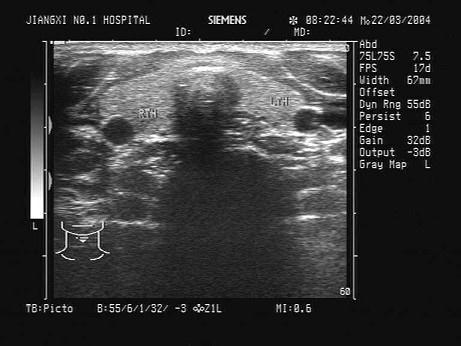

问题 如图,正常甲状腺中部横切面的超声声像图,中央气管环状软骨前方组织为?(?)

选项 A.甲状腺峡部 B.皮下组织 C.甲状旁腺 D.淋巴结 E.以上均不对

答案 A